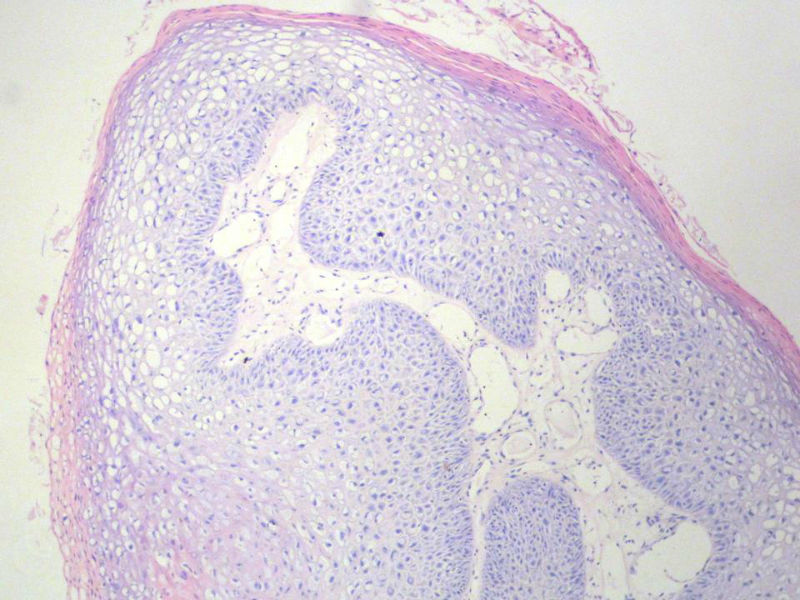

男,72岁,右耳听力下降两个月,检查右外耳道有黄豆大肿物,表面乳头状,手术切除。

乳头状瘤

乳头状瘤,有轻度异形,有恶变倾向

乳头状瘤,上皮内可见挖空样细胞,建议HPV检测

鳞状上皮乳头状瘤,未发现恶性变。